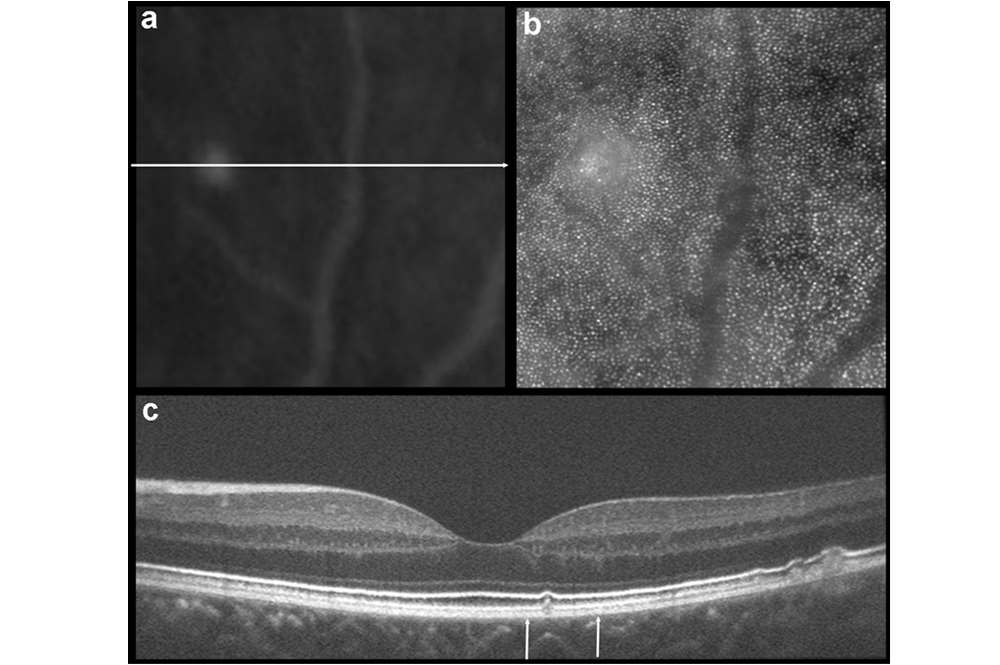

Drusen

Multimodal imaging of an isolated druse. Top left is a magnified fundus autofluorescence image, top right is the corresponding photoreceptor mosaic seen with adaptive optics, bottom is an OCT B-scan of the same druse.